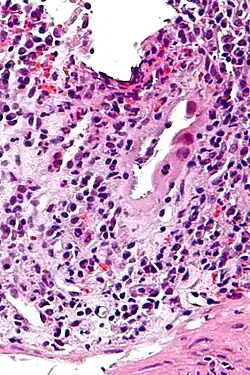

| Micrograph of CMV colitis. H&E stain. | |

CMV colitis may be clinically manifested with diarrhea (usually non-bloody), abdominal pain, weight loss and anorexia. The diagnosis of CMV colitis is based on serology, CMV antigen testing and colonoscopy with biopsy. CMV colitis usually occurs in immunocompromised patient and is much rarer in immunocompetent patients. Although it is known that CMV colitis is almost always caused by reactivation of latent CMV infection in immunocompromised patients, new infection of CMV or reinfection of different strain of CMV can cause colitis in immunocompetent hosts. Because asymptomatic CMV viremia and viruria is common and about 1/3 of symptomatic CMV infection is caused by reinfection of different strain of CMV, the diagnosis of CMV colitis needs more direct causality. It is practically achieved by colonoscopy or sigmoidoscopy tissue sampling and pathological evidence of CMV infection under microscope, more specifically macroscopic picture will show many ulcers that appear on the mucous membrane and microscopically the biopsy will show intranuclear and cytoplasmic inclusion bodies. Positive CMV IgG doesn't necessarily mean that it is reactivation of latent infection because of the possibility of reinfection of different strain.